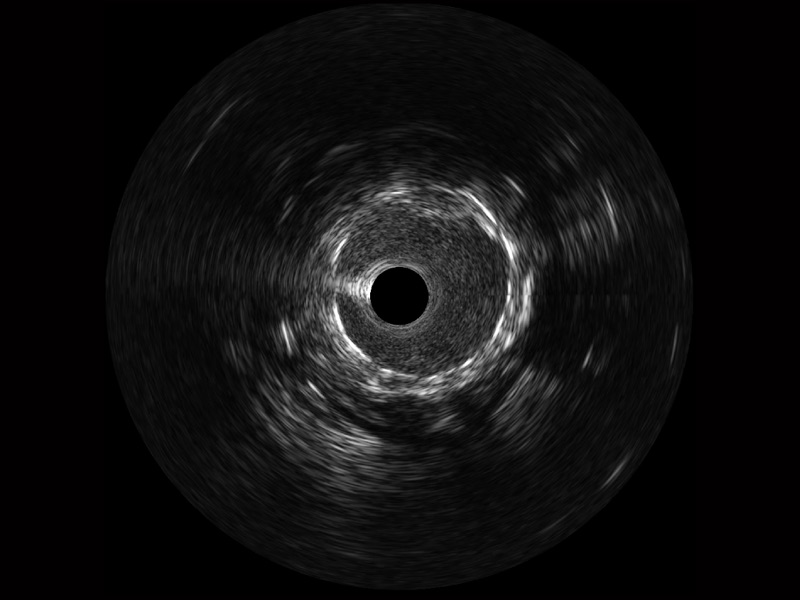

九州酷游宽频IVUS图像

对比传统IVUS导管成像,九州酷游宽频IVUS图像的近场支架梁显影更细腻,远场中膜外血管仍清晰可辨,兼顾远中近,兼顾分辨力与穿透深度